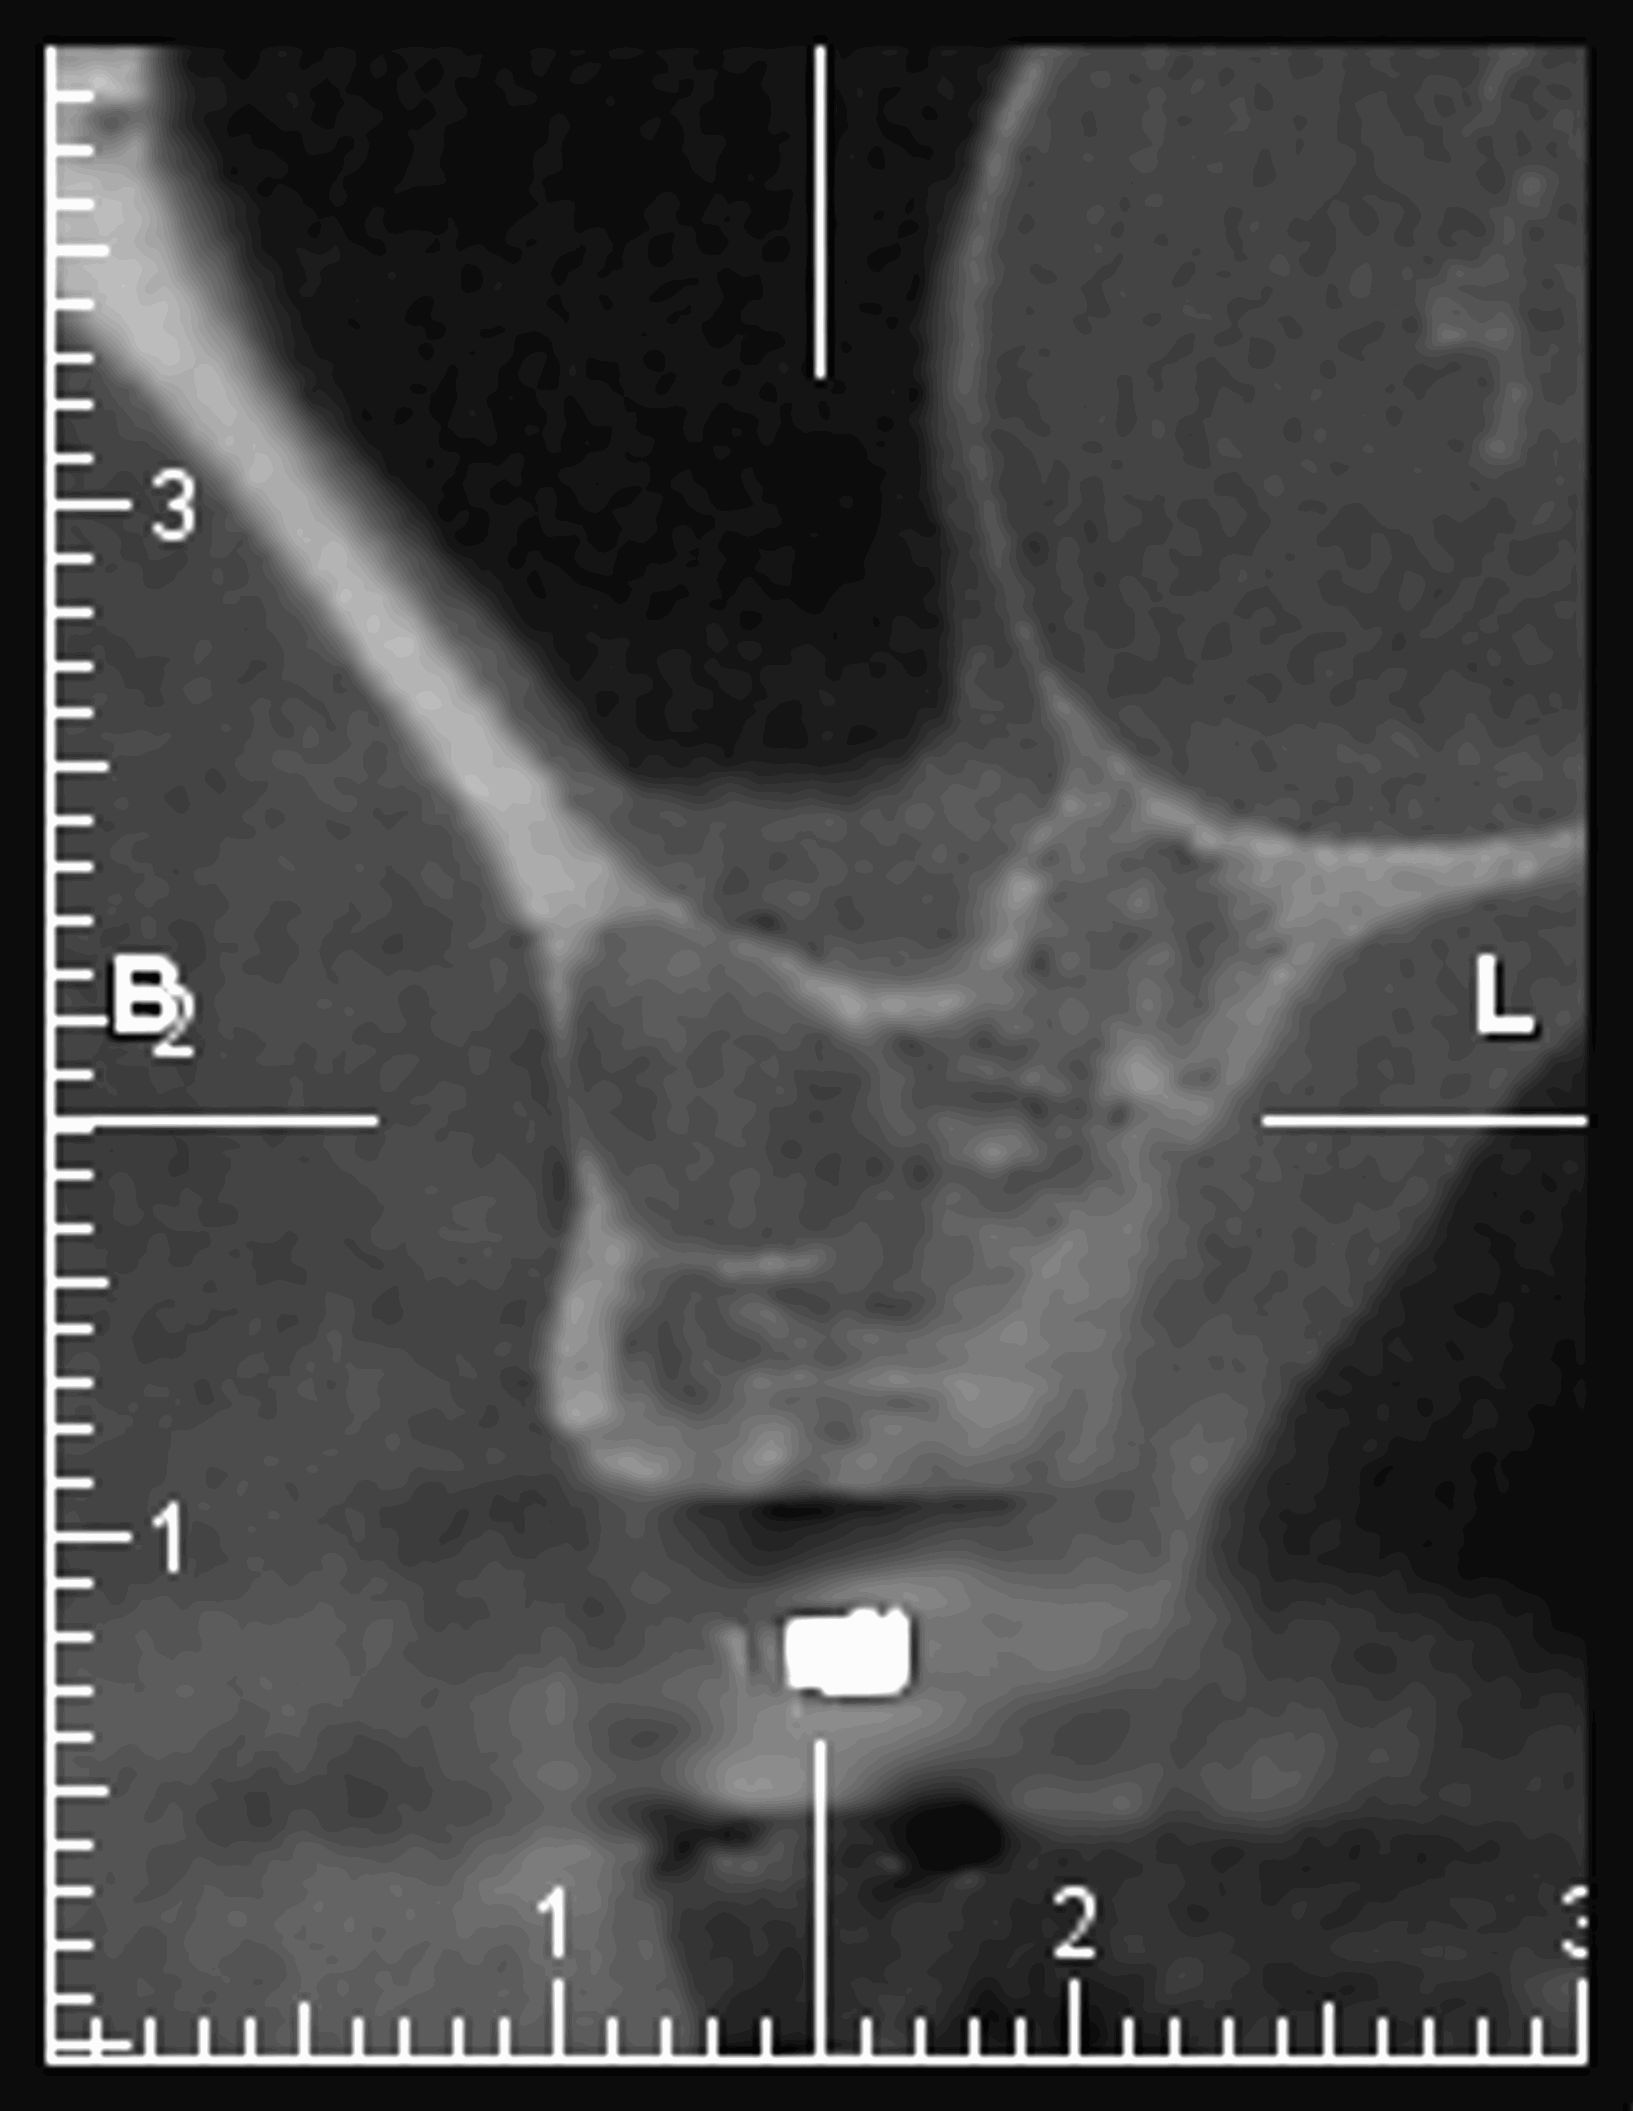

Le cone beam est une nouvelle technique de radiographie numérisée situé entre le panoramique dentaire et le scanner, il utilise un faisceau d’irradiation de forme conique d'où son nom. Cet appareil présente notamment l’avantage d’être plus précis que le panoramique dentaire et il possède une résolution similaire, voire supérieure à celle du scanner, avec en plus la possibilité d’une reconstruction numérique en 3D.

Il permet de balayer en un seul passage l’ensemble du volume à radiographier et en étant moins irradiant que le scanner.

Le cone beam utilisé en pathologie dentaire et maxillo-faciale est indiqué pour l’examen des tissus minéralisés (dents, cartilages, os), il permet d’identifier les lésions osseuses, les fractures, les infections, les kystes ou les corps étrangers.

Il est un examen de choix en implantologie.

Il ne permet pas d’étudier les tissus mous, ni de mesurer la densité contrairement au scanner.

Il évalue au plus juste le volume osseux et la position des structures anatomiques comme les nerfs en vue de la pose d’implants. La modélisation en 3D permet la taille et la forme des implants proportionnellement à la morphologie du patient et de simuler virtuellement leurs emplacements.

Les nouvelles générations de scanner permettent de faire une acquisition d’un volume global d’une partie du corps et de travailler à l’intérieur de ce volume en isolant une structure anatomique donnée et de l’explorer dans tous les plans de l’espace.

Grace à la technique de seuillage il est possible de dissocier progressivement les dents des structures osseuses environnantes dans le volume donné.